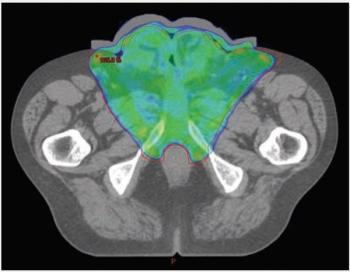

“MK,” a man aged 67 years, presented with fatigue and nausea to his primary care physician. CT staging scans confirmed the primary tumor and a suspicious left 1.2-cm inguinal lymph node but no distant metastases. MRI of the pelvis revealed complete replacement of the penis with tumor as well as invasion into the scrotum and bilateral groin soft tissue; additionally, early pubic bone invasion was present, with left groin lymphadenopathy. Biopsy verified squamous cell carcinoma of the penis, and discussion with the multidisciplinary team uroradiologist confirmed bony invasion.